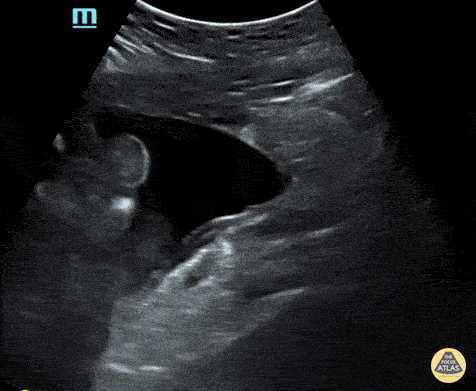

Peds-Trauma

abnormalluq, abnormalruq, msk, traumanormal